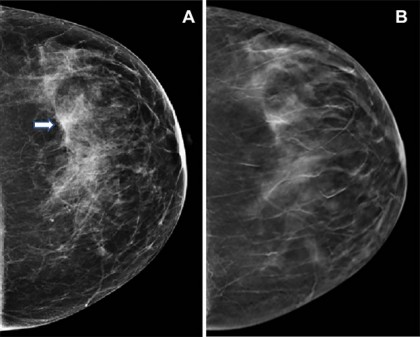

foto: Imagini la o femeie de 47 de ani care s-a prezentat la screening de rutină. (A) Mamografia digitală arată densități fibroglandulare împrăștiate. Pe partea stângă a mamografiei digitale este prezentă o asimetrie (săgeată). (B) Imaginea de tomosinteză digitală a sânului nu arată nicio leziune suspectă, ci mai degrabă o suprapunere a structurilor fibroglandulare și ligamentare normale. https://doi.org/10.1148/radiol.221571 © RSNA 2023

Mamografia digitală bidimensională (2D) utilizează o singură imagine plată pentru a obține o imagine a țesutului mamar, ceea ce poate duce la suprapunerea țesutului și poate face mai dificilă detectarea unor anomalii. În schimb, tomosinteza digitală a sânilor utilizează imagini multiple pentru a crea o imagine tridimensională a sânilor, ceea ce reduce suprapunerea țesutului și poate face mai ușor detectarea anumitor tipuri de anomalii, în special a celor mai mici și mai subtile.